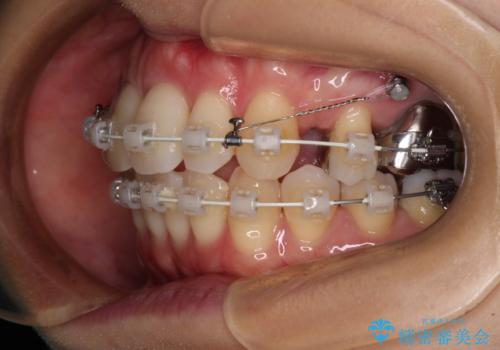

上下の咬み合わせは上顎歯列全体が歯1本分前にずれている状態であり、さらに上顎歯列はV字型に尖っていたため、上下前歯は全く接触していない状態でした。

上顎左右第一小臼歯を抜去して、ワイヤー装置にて口元の突出感を改善するよう矯正治療を行うこととしました。